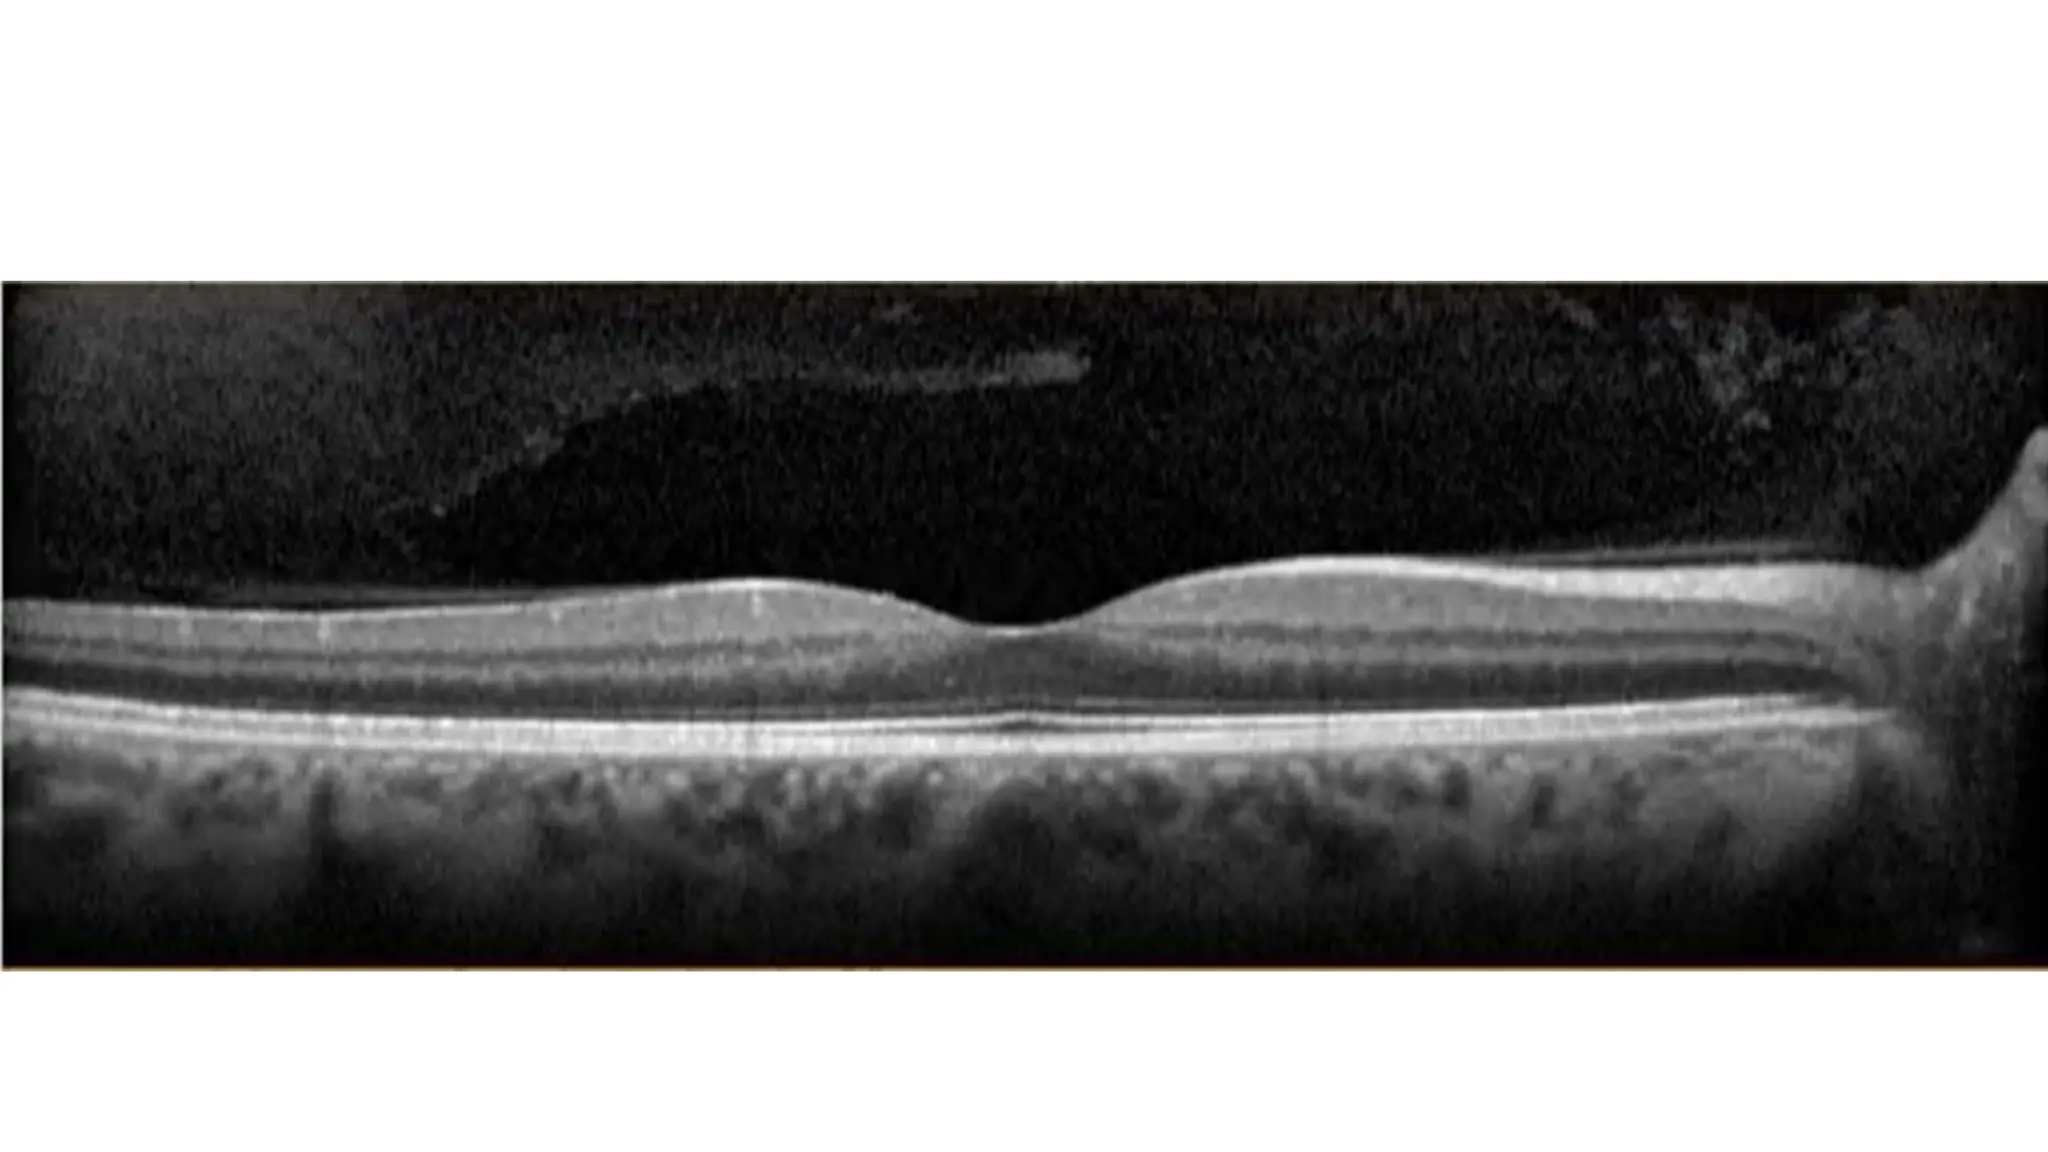

The document discusses various stages of posterior vitreous detachment (PVD) and associated ophthalmological conditions. It highlights the classification of PVD stages, including no PVD, paramacular PVD, and complete PVD, alongside related factors like traction and retinal issues. Key acronyms and terms relevant to diabetic retinopathy and retinal morphology are also mentioned.